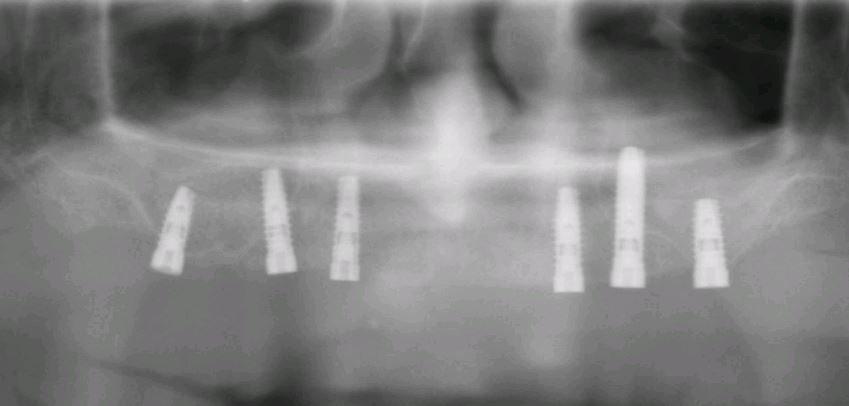

Sind nun alle Zähne des Kiefers verloren gegangen oder ist es notwendig alle restlichen Zähne zu entfernen, bleibt den Patienten normalerweise nichts anderes als eine konventionelle Vollprothese. Hier kann durch das spezielle Verfahren des Einbrigens von vier Implantaten ein Zahnersatz bereits in sehr zügiger Weise im Mund befestigt werden. Diese Methode ist an bestimmte Vorgaben gebunden und nicht immer ohne weiteres anwendbar. Bei günstigen Bedingungen kann es sogar möglich sein sogenannte "feste Zähne an einem Tag" zu bekommen.

Miniimplantate

"Schnelle Hilfe bei losen Prothesen"

Vielen Menschen ist nach Jahren oder gar Jahrzehnten der Zahnlosigkeit und dem Tragen von Vollprothesen die Problematik sehr gegenwärtig. Neben dem oft mangelhaften Sitz der Zahnprothesen gibt es immer wieder schmerzhafte Druckstellen, die Sprachbildung ist erschwert und das Zerbrechen dieser Kunstoffzähne ist immer eine Gefahr. Aber gerade ältere Menschen stehen einer operativen Implantatbehandlung skeptisch gegenüber. Sie fürchten die Dauer der Behandlung oder haben Bedenken wegen einer möglicherweise eingeschränkten allgemeinen Gesundheitsverfassung. Hier bietet die minimalinvasive Implantologie Abhilfe. Durch das spezielle Design von sogenannten -Miniimplantaten- kann eine aufwändigere Operation vermieden werden. Das Einbringen dieser Implantate kann dann auch ohne ein chirurgisches Schneiden der Kieferschleimhaut geschehen. Natürlich ist bei diesem minimalinvasivem Vorgehen eine zuverlässige Vermessung mit Hilfe von 3D-Röntgen notwendig um eine genaue Position der Implantate zu erzielen und keine Verletzungen oder Schäden zu verursachen. Auch hier kann bereits am Tag des Eingriffs die gewünschte Verbeserung des Haltes der Prothesen durch die eingearbeiteten Druckknöpfe erreicht werden.